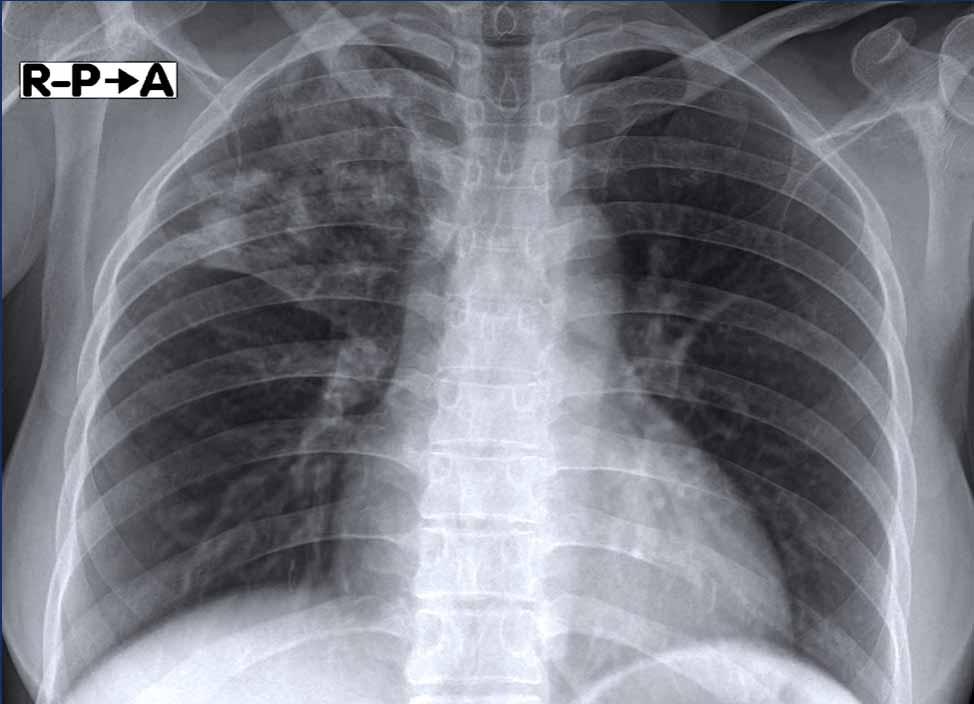

Hình ảnh này của một nữ bệnh nhân 36 tuổi có biểu hiện đau ngực, ho và sốt.

Hình ảnh

Đông đặc đậm ở thùy trên phải kèm mất thể tích nhẹ.

Xét nghiệm đờm dương tính với lao.